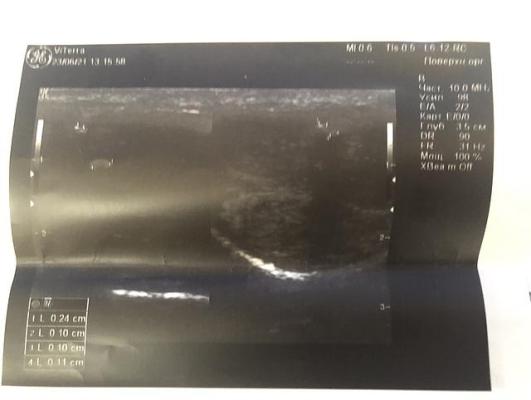

Через 4 месяца лечения при УЗИ полового члена определяются гиперэхогенные включения с умеренной эхо-тенью в проксимальной трети дорзально 2.5х1.5 мм (фрагментирована на два элемента) и между кавернозными телами 2.5х1.5 мм, дистально - два включения 2.5х1 мм и 1х1 мм дорзально, между кавернозными телами - не определяются.